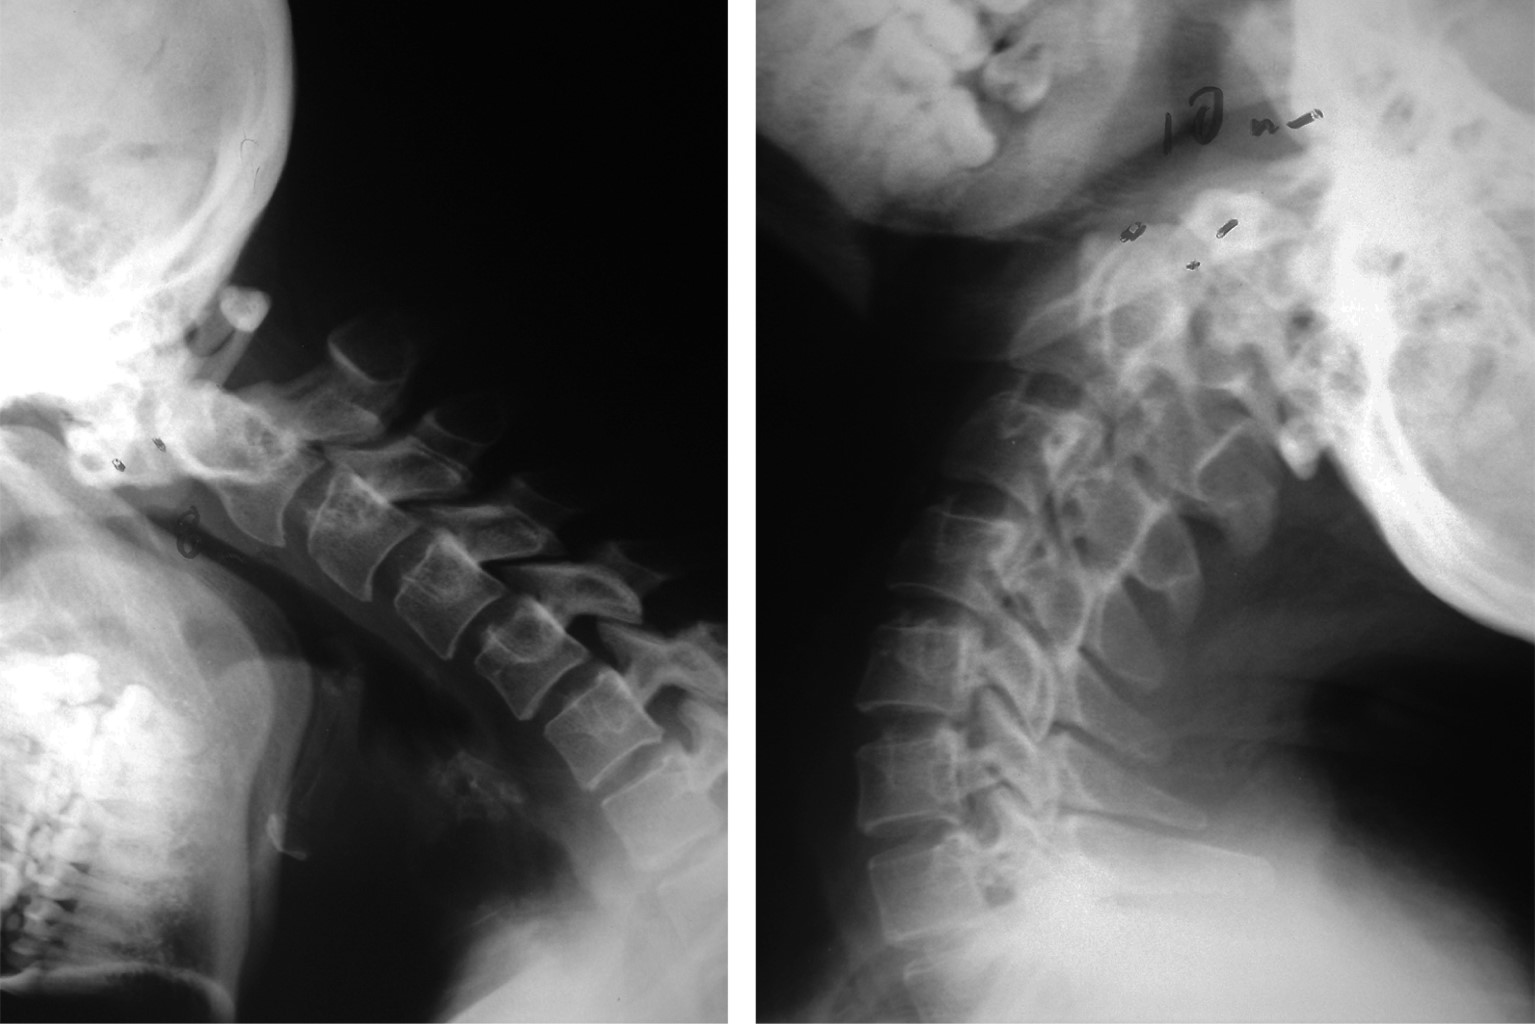

The os odontoideum is a variable oval or round ossicle with a smooth cortical border, which partially corresponds to the odontoid process, without having continuity with the rest of C2 bone. The multifactorial etiology causes instability and clinically translates into pain and compression data into neural structures. The treatment of choice is surgical and techniques have been developed that focus on preserving the stability of the segment. We present the case of a 23-year-old female patient, who begins to suffer at 8 years of age, refers to moderate to severe cervicalgia, which develops with paresthesias in the left hemisphere and later paresis of the left thoracic limb. Physical examination showed hypoaesthesia of the left hemisphere, as well as paresis of the left thoracic limb. Extension studies demonstrate chronic axonal lesion from C1 to C3, predominantly left, imaging studies showing axial instability and magnetic resonance bulbar compression. The patient receives surgical treatment consisting of posterior fixation C1-C2, evolving satisfactorily.

Figure 2